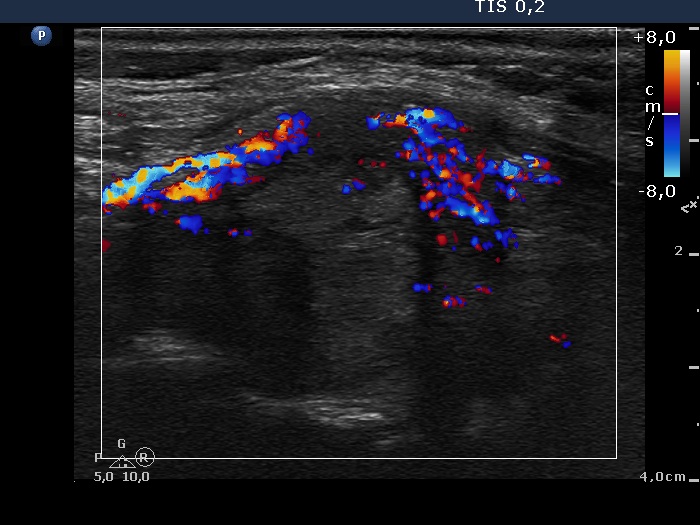

Follow-up investigation 11 months after the initial one (ultrasonographic picture 8)

Left lobe, longitudinal scan, color Doppler mode. The vascularization of the extranodular part of the lobe became significantly increased.